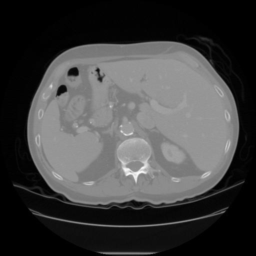

The qualitative results for the proposed and competing methods are shown in Fig. 3. The quantitative results comparison of the proposed method to the four state-of-the-art methods are shown in Table 1. The results reveal that the proposed method comfortably outperform other studied methods for smaller fractions of annotated data (e.g. Spleen 5%). The gap between the Duo-SegNet and other competitors decreases on the Nuclei dataset, when the amount of labeled data increases. That said, we can still observe a significant improvement on the Heart and Spleen dataset. The proposed network can produce both accurate prediction masks and confidence maps representing which regions of the prediction distribution are close to the ground truth label distribution. This is useful when training unlabeled data. Fig. 2 shows the visual analysis of confidence maps.

| Input | GT | Prediction | Confidence Map |

Spleen |

![]() |

| Input | GT | Fully Supervised | Mean Teacher | Pseudo Labelling | VAT | Deep Co-training | Duo-SegNet (Ours) |